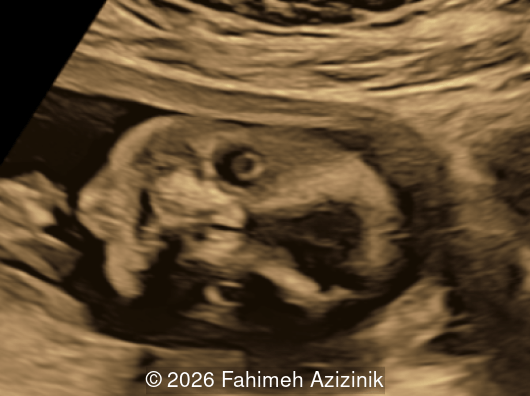

A 36-year-old pregnant woman (G2P1) was referred at 18 weeks and 4 days gestation to our tertiary center for sonographic evaluation due to the suspicion of various fetal anomalies.

Image 1

We present a case of Apert Syndrome.

Our ultrasound examination revealed the following findings:

• Bicoronal craniosynostosis

• Hypertelorism

• Frontal bossing

Bicoronal synostosis is the characteristic cranial hallmark of Apert syndrome, detectable sonographically from 18 weeks. Its most recognizable manifestation is turribrachycephaly, defined by an elevated cephalic index (typically >85–90%) and a tall cranial vault with marked frontal bossing [19]. On prenatal ultrasound, the face in Apert syndrome shows midface hypoplasia with a depressed nasal bridge, proptosis, hypertelorism, and frontal bossing. The extremities demonstrate syndactyly of both bone and soft tissue of the hands and feet with partial-to-complete fusion often involving second, third, and fourth digits, known as “mitten hands” and “socked feet”. In severe cases, all digits are fused, with the presence of a single nail known as “synonychia” [20]. Other ultrasound findings include mild ventriculomegaly, agenesis of the corpus callosum, deficient or absent septum pellucidum, and fusion of the cervical vertebrae at the level of C5-C6 [21]. Cardiovascular (atrial and ventricular septal defect) and genitourinary anomalies (hydronephrosis, and cryptorchidia) are present in 10% of patients [22]. Increased nuchal translucency in the first trimester [23], widely open metopic suture [24], and polyhydramnios [25] have also been reported. Three-dimensional (3D) ultrasound facilitates assessment of surface abnormalities of the face and extremities, and magnetic resonance imaging (MRI) can be used to evaluate associated intracranial conditions [26].